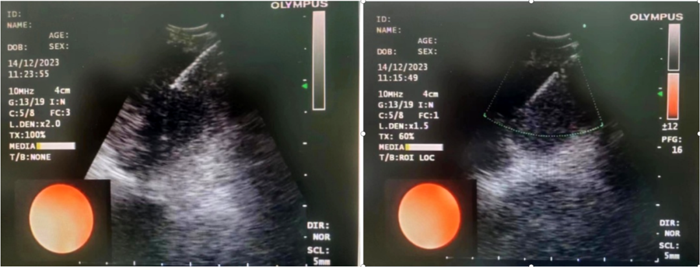

患者,女,72歲,2月來“反復(fù)咳嗽、咳痰,偶咳白痰中帶血絲”,胸部CT提示“肺占位、肺炎”,收住院。完善胸部強化CT提示“左肺占位、肺炎、縱膈多發(fā)淋巴結(jié)腫大”,電子支氣管鏡檢查見左肺上葉支氣管血塊及壞死物阻塞,清除后見管腔通暢,刷檢DNA細胞學(xué)示“細胞退變明顯,建議進一步檢查”。10月27日行CT引導(dǎo)下肺穿刺活檢,病理示“機化性肺炎”,給予抗感染及激素治療,患者癥狀好轉(zhuǎn)出院。半月前,患者復(fù)查肺CT發(fā)現(xiàn)病灶較前稍有增大,張強主任考慮患者癥狀雖有好轉(zhuǎn),但仍存在腫瘤性病變可能性。經(jīng)過討論及與患者家屬充分溝通后,決定實施支氣管內(nèi)超聲引導(dǎo)下針吸活檢術(shù)(EBUS-TBNA)+電子支氣管鏡檢查+現(xiàn)場快速評價(ROSE)技術(shù),以提高診斷陽性率。術(shù)中ROSE提示查找到可疑癌細胞,取材量較足分。最后病理檢查明確診斷為低分化肺腺癌,隨后進行基因檢測,明確了治療方向。

患者,男,70歲,近2個月來“活動后呼吸困難,近日又出現(xiàn)痰中帶鮮血”,收住院。胸部增強CT見“左肺下葉外周型占位,肺門、縱膈淋巴結(jié)腫大”。張強主任帶領(lǐng)團隊討論分析患者病情,高度懷疑為腫瘤性病變,且普通電子支氣管鏡獲取組織困難,病變緊貼主動脈,經(jīng)皮肺穿刺活檢風(fēng)險大。為明確診斷及分期,決定為患者實施支氣管內(nèi)超聲引導(dǎo)下針吸活檢術(shù)(EBUS-TBNA)+電子支氣管鏡下病灶活檢+現(xiàn)場快速評價(ROSE)。術(shù)中ROSE快速診斷查找到肺腺癌細胞,手術(shù)過程順利。最后病理檢查明確診斷為肺腺癌,為患者的下一步治療確定了方向。